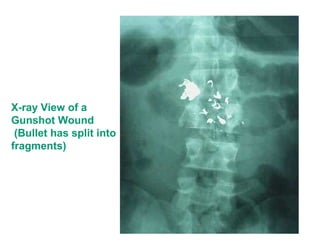

X-ray View of a

Gunshot Wound

(Bullet has split into

fragments)

X-ray View ofa Gunshot Wound (Bullet has split into fragments)